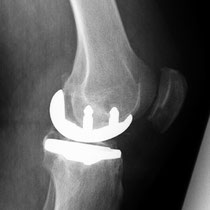

Auch bei dem künstlichen Ersatz des Kniegelenkes muss genau abgewogen werden, was eingentlich ersetzt werden muss. Je weniger ersetzt wird umso besser im Gesamtergebnis. Warum soll man das ganze Knie ersetzen, wenn nur der Knorpel unter der Kniescheibe zerstört ist (Bild 3 Kniescheiben - und Gleitlagerersatz). Anders bei schwerer Rheumazerstörung, bei der alle Bänder ausgelockert sind - hier wäre die normale Knieprothese auch locker (Bild 5 Lösung: achsgekoppelte Prothese). Ich versuche für meine Patienten das bestmögliche Implantat auszusuchen. Für Allergiker stehen spezielle titanbeschichtete Kniegelenke zur Verfügung.